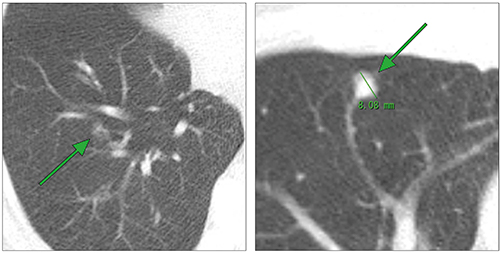

実際の読影においても,5mm以上の病変を検出することは多くの経験論からも否定されるものではないが,図2に示すように,小結節におけるすりガラス影部分と部分容積効果によるすりガラス影の区別が困難な症例が発生し,充実成分の大きさの評価は不十分と想定される。これに対しPrionasら6)は,充実性病変を模擬したファントムを用いてCT画像上の体積計測精度を検証し,真の体積に対しスライス厚の増加とともにCT画像上の体積が小さくなることを報告している(図3)。また,「1.CTDIvol“2.5mGy”の妥当性」の項目で参考とした3つの標準プロトコルでは,スライス厚は2.5mm以下と規定され,いずれも1.0mm以下を推奨している。

図2 5mmスライス厚の問題点

(画像は小諸厚生病院放射線科・丸山雄一郎先生のご好意による)

Ⅰ. 5mm以上の結節検出は可能

Ⅱ. Pure GGOと部分体積効果のすりガラス影の判定が困難

Ⅲ. サイズに関して肺がんCT検診でのフォローアップでは評価が困難